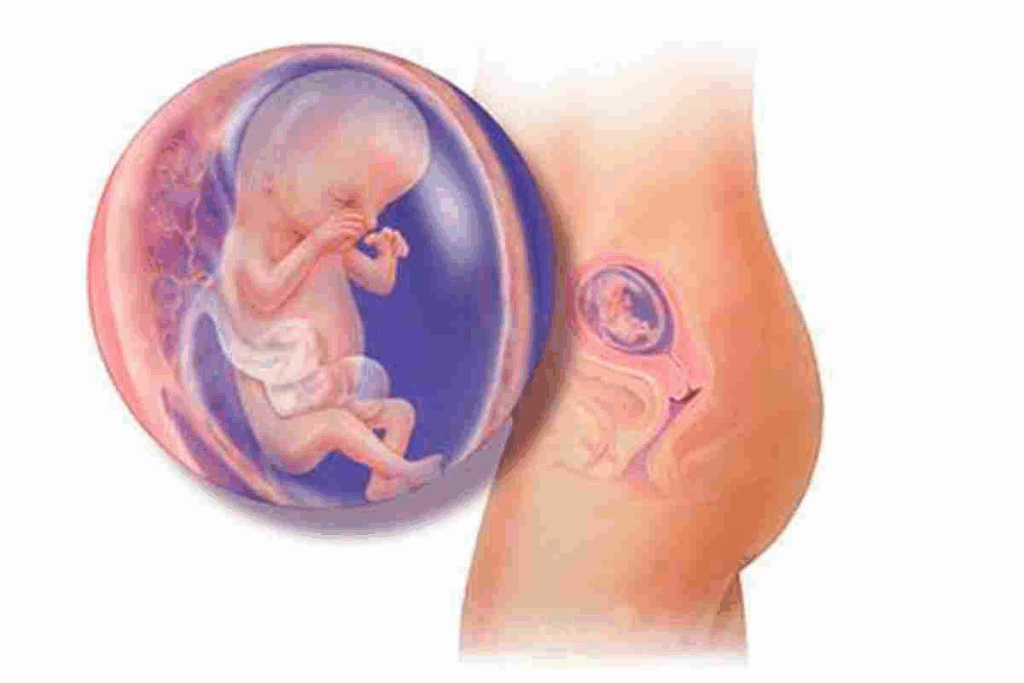

What Happens in Your Body at 3 Weeks Pregnant

At 3 weeks pregnant, a new life starts with fertilization. This is a key time for your embryo’s development.

The Fertilization Process

Fertilization happens when a sperm meets an egg in the fallopian tube. It usually takes 6 to 12 days after sex. This is when pregnancy begins, creating a zygote that starts its journey to the uterus.

The journey of the fertilized egg is complex. It involves many cell divisions as it moves down the fallopian tube. The fertilized egg, now called a blastocyst, gets ready to implant in the uterine lining.

Embryo Development Timeline

Knowing the embryo development timeline helps understand early pregnancy. Here’s a quick look:

Day | Development Stage |

1-3 | Fertilization and initial cell divisions |

4-5 | Formation of blastocyst |

6-12 | Implantation in the uterine lining |

At 3 weeks pregnant, the embryo grows fast. It’s a time when the fetus’s major organs and systems start to form.